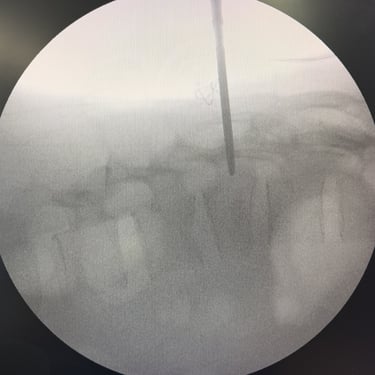

Fractura Vertebral Lumbar: Estabilización Segura con Fijación Transpedicular (FTP)

La fractura vertebral lumbar es una lesión que puede comprometer la estabilidad de la columna y las estructuras neurológicas. En casos seleccionados, el tratamiento quirúrgico mediante artrodesis con fijación transpedicular (FTP) ofrece una estabilización sólida de los segmentos afectados, restaurando la alineación vertebral y permitiendo una movilización temprana. Esta técnica reduce el dolor, previene deformidades progresivas y protege las raíces nerviosas. La intervención oportuna, acompañada de una adecuada rehabilitación, contribuye a una recuperación funcional segura y a una mejora significativa en la calidad de vida del paciente.